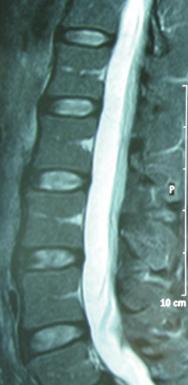

Slika 1: Normalna ledvena hrbtenica mlajšega moškega v stranski projekciji, preiskava z magentnoresonancnim tomografom. Vidna je segmentalna zgradba hrbtenice